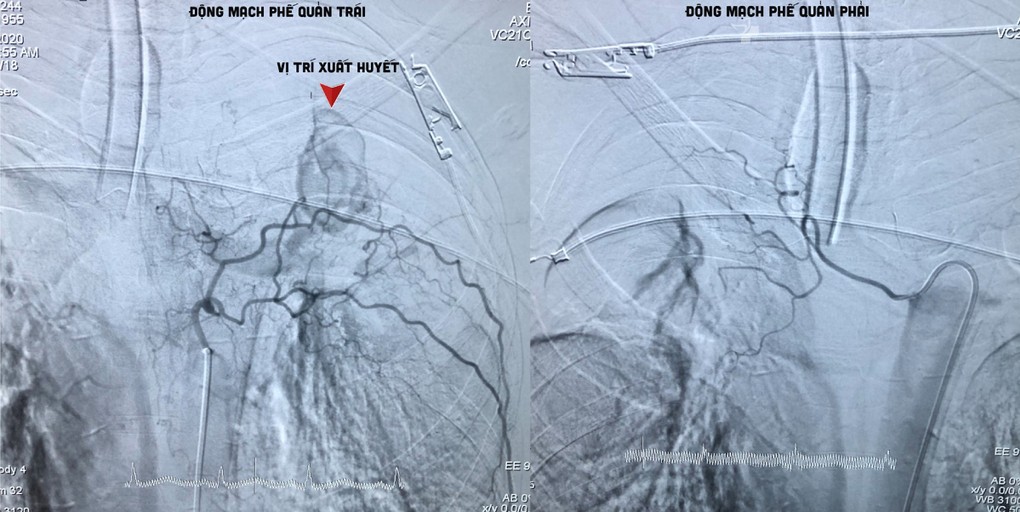

Sau khi xem xét, đánh giá tình hình, các bác sĩ quyết định can thiệp xử lý nội mạch, bằng kỹ thuật nút tắc động mạch phế quản cầm máu BAE (bronchial artery embolization) đối với bệnh nhân.

Dưới màn hình tăng sáng của máy chụp mạch số xóa nền (DSA), bác sĩ đặt một ống thông nhỏ đi từ động mạch đùi đến động mạch phế quản đang chảy máu. Sau đó, một ống thông có kích thước nhỏ hơn tiếp tục được luồn một cách chọn lọc vào trong lòng động mạch phế quản bị tổn thương để bơm chất nút mạch.

Sau can thiệp, các mạch máu động mạch phế quản gây tình trạng xuất huyết đã được nút lại kịp thời. Bệnh nhân qua cơn nguy kịch.